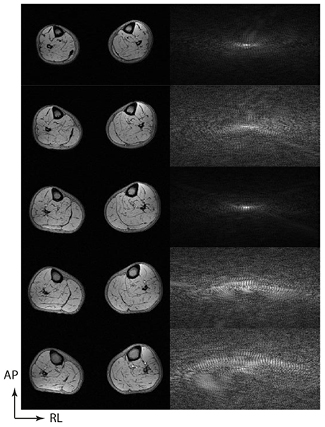

Consider the transverse image of the lower leg muscles in figure 6(a), which is derived from fully-sampled data. If we transform the image with a discrete wavelet transform, the signal energy is compressed into a small number of wavelet coefficients with significant intensity. If we apply an irregular undersampling pattern, such as that shown in figure 6(b), then the inverse Fourier transform now shows evidence of noise in the image domain, but no structured aliasing, and the degree of degradation increases with the degree of undersampling (figures 6(c) and (d)). The image degradation arises as there is leakage of signal energy from each pixel into neighbouring pixels in the image domain. This artefact is also not structured in the wavelet domain, the most significant wavelet coefficients appear near-identical for fully sampled and undersampled images. But we already know from figure 5 that by keeping only the most significant coefficients we can reconstruct a high-quality image. By enforcing sparsity in the wavelet domain we limit the reconstruction of the image to the highest intensity wavelet coefficients which permit the reconstruction.

Figure 6. Examples of Cartesian variable density Poisson disk undersampling patterns with different accelerations. The phase encoding space of a 3D gradient echo (ky–kz plane) is shown for (a) a full Nyquist criterion acquisition and accelerations of (b) 3.65 ×, (c) 4.94 × and (d) 6.42 ×. In each case a Poisson disk with a quadratic fall off in sampling density has been designed, with a fully sampled centre portion to permit parallel imaging to be combined with compressed sensing using L1-ESPIRiT. In the middle column we see the effect of the sampling pattern if an inverse Fourier transform is performed. For (b), (c) and (d), there is no structured aliasing, but there is impaired image quality. Examining the discrete wavelet transforms of these acquisitions (right column) shows no discernible difference by eye.

Download figure:

Standard image High-resolution imageThis means that the sparsity of the original image in the discrete wavelet domain can be used to retrieve the original image from a small number of wavelet coefficients. This example enables us to see the pre-conditions of compressed sensing very clearly. If we had not used an irregular undersampling pattern, but had done a regular k-space undersampling such as is used in conventional parallel imaging, then the Fourier transformed image space would have contained structured aliasing, and this structured aliasing would have been contained, within the same highest intensity coefficients of the wavelet domain as the image proper, preventing us from recovering an artefact-free image by enforcing sparsity in the wavelet domain.

Two reconstruction methods for parallel imaging with arbitrary undersampling were proposed by the group of Lustig, SPIRiT (Lustig and Pauly 2010) and e-SPIRiT (Uecker et al 2014), which operate in the k-space and image domains, respectively, and can incorporate an L1-norm minimization term to additionally enforce sparsity in a transform domain. In order to derive the sensitivity map information using these methods, the undersampled k-space acquisition will need to either possess a fully sampled area at the centre of k-space, or for such data to be available from a previous acquisition. In all that follows, it will be assumed that the fully sampled centre portion of k-space is being acquired together with an undersampled peripheral k-space (figure 6), as this has been the most common way that combined compressed sensing and parallel imaging (CS-PI) has been performed.

Critically the purpose to which the images with compressed sensing images are put will determine the maximum acceleration. In the case of the reconstructed CS-PI muscle images shown in figure 9, the images appear qualitatively equivalent, though with increasing acceleration, there is some loss of high frequency features (such as minor fasciae), which make the muscle groups harder to differentiate. The data were acquired for the purpose of monitoring fat content in particular muscle groups and two independent observers concurred that a 5× acceleration was the maximum compatible with defining all the desired muscle groups (Hollingsworth et al 2014). However, had only the total muscle volume been desired then the 6.42× acceleration acquired (and possibly higher accelerations) would also have been acceptable.

Figure 9. Examples of combined compressed sensing and parallel imaging reconstructions of fat fraction maps for the calf muscle of a subject with Becker muscular dystrophy. The figure compares full Nyquist sampling with accelerations performed using variable density Poisson disk acquisitions at 3.65×, 4.94× and 6.42×. The reconstruction quality is found to be very good: in the broader series, some muscle groups cannot be segmented on the 6.42× acceleration images (Hollingsworth et al 2014).